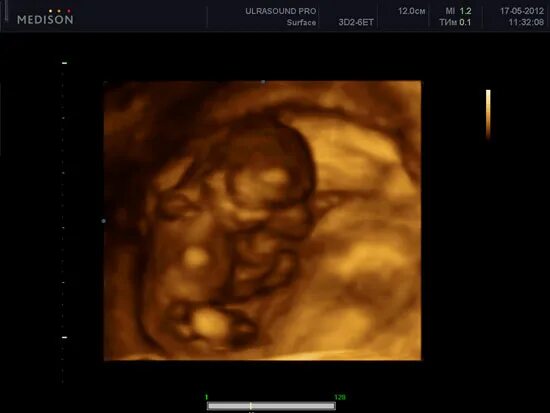

Как проходит первый скрининг в 12 недель